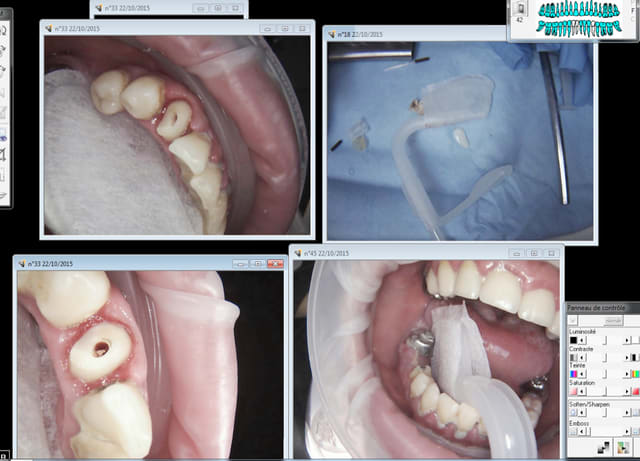

Je vais essayer de prendre quelques photos pour illustrer ses utilisations; J'aimerais bien avoir l'avis d'autres utilisateurs qui ont déjà testés le capodent, par curiosité :)